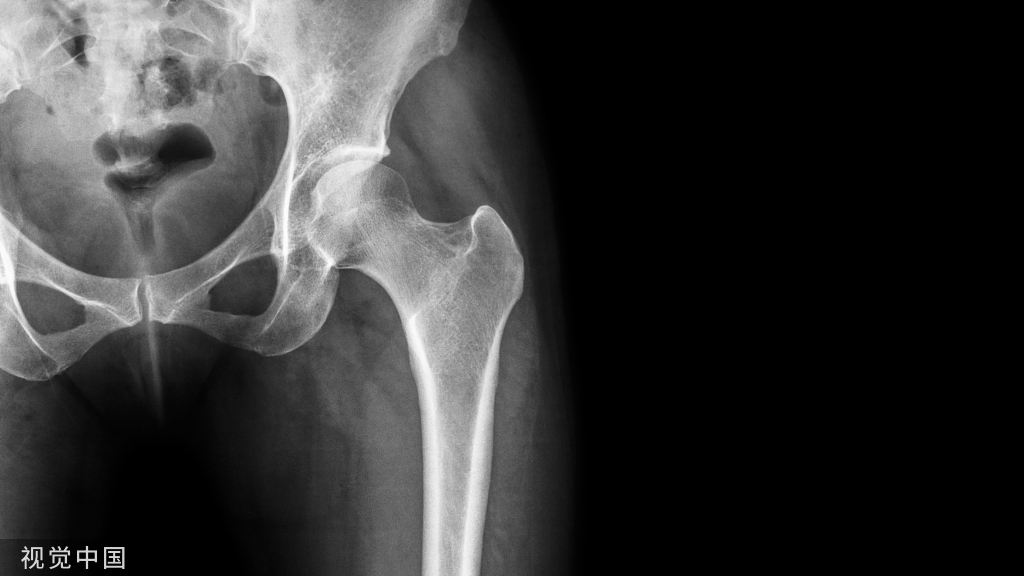

4部分骨折

注意完成内侧支撑和内外翻的复位

在此病例中,为了复位良好,舍弃了肱骨近端与钢板贴服